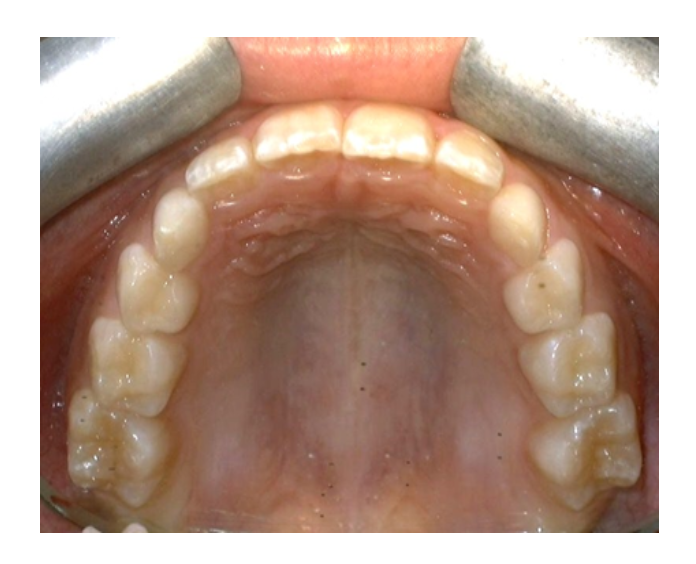

Ortodoncia

temprana